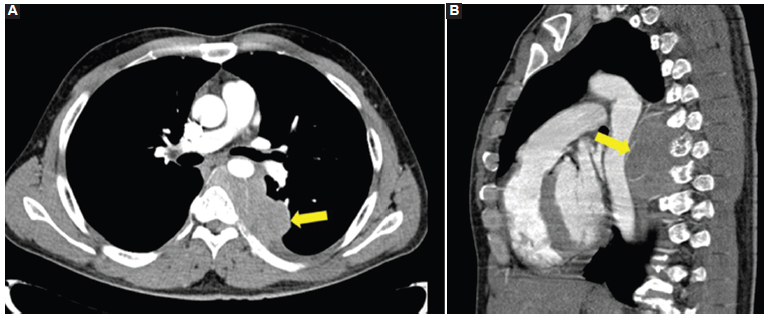

Se solicitaron radiografías de tórax de frente y de perfil, que mostraron una masa en el mediastino posterior (Fig. 1). Para mejor caracterización se realizó una tomografía computada (TC) de tórax, en la que se confirmó la presencia de una voluminosa tumoración sólida ubicada en el tercio medio del mediastino posterior, lateralizada a la izquierda, hipodensa, homogénea y con escaso realce del medio de contraste (Fig. 2). Desplazaba las estructuras mediastinales adyacentes, sin invadirlas, y por su sector posterior se introducía en el canal raquídeo. A pesar del amplio contacto óseo con los cuerpos vertebrales y los arcos costales, la única alteración observada fue en los arcos costales izquierdos, en los que producía un mínimo adelgazamiento de la cortical, sin interrupción de la misma.